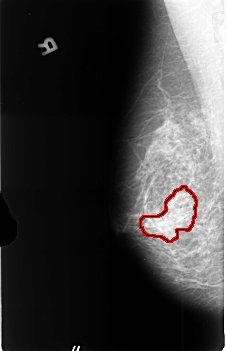

B_3441_1.RIGHT_MLO

FILE: B_3441_1.RIGHT_MLO.OVERLAY

TOTAL_ABNORMALITIES 1

ABNORMALITY 1

LESION_TYPE CALCIFICATION TYPE PLEOMORPHIC DISTRIBUTION CLUSTERED

LESION_TYPE MASS SHAPE IRREGULAR MARGINS OBSCURED-ILL_DEFINED

ASSESSMENT 3

SUBTLETY 2

PATHOLOGY MALIGNANT

TOTAL_OUTLINES 1

BOUNDARY